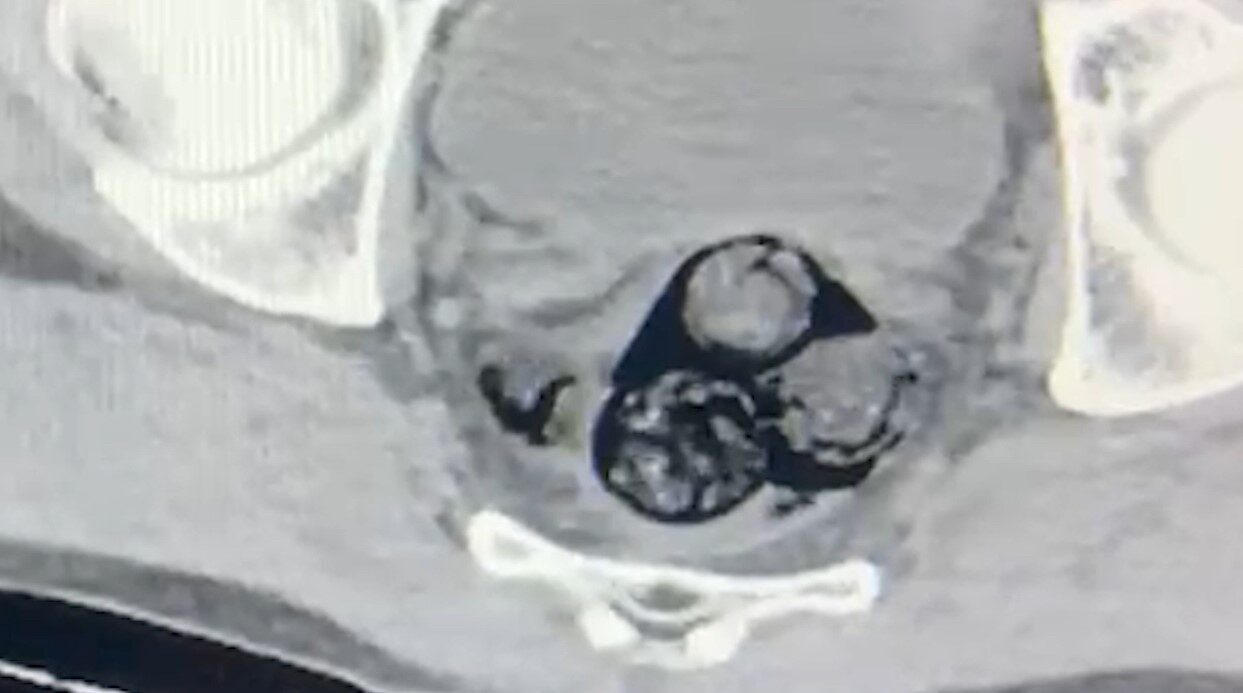

Iğdır İl Emniyet Müdürlüğü Narkotik Suçlarla Mücadele Şube Müdürlüğü’ne bağlı ekipler, A.İ.’yi yakın takibe aldı. Gerçekleştirilen ayrıntılı aramalar, şahsın vücut boşluklarında uyuşturucu madde bulundurulduğunu ortaya çıkardı. Radyolojik inceleme sırasında, A.İ.’nin makat bölgesinde dört ayrı yabancı cisim tespit edildi.

Sağlık kontrolünden geçirilen şüpheli şahısın vücudundan çıkarılan cisimlerin içeriğinde toplamda 140 gram metamfetamin bulundu. Uyuşturucu madde bulundurmak ve ticaretini yapmak suçlamasıyla hakkında işlem başlatan güvenlik güçleri, A.İ.’yi Iğdır Adliyesi’ne sevk etti.